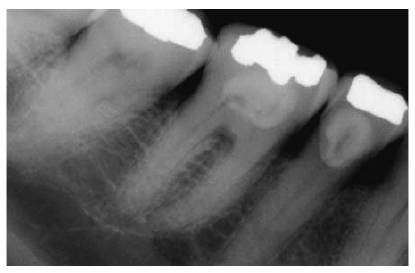

In most cases, an endodontic procedure should not be initiated without

evaluating at least two recent radiographs exposed at different horizontal

angulations of the suspected tooth (Figures 19-24A

and B).

Comparing varied views is essential in diagnosing the presence of additional

roots, anatomic configurations, anomalies, and other unusual circumstances that

may complicate the treatment.

Figure 19-24A and B: (A) Pretreatment radiograph of a mandibular premolar shows one canal. (B) A second radiograph taken from an angulation of 15 degrees from the mesial discloses a second root.